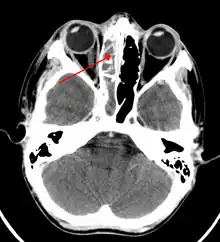

Frontal sinusitis